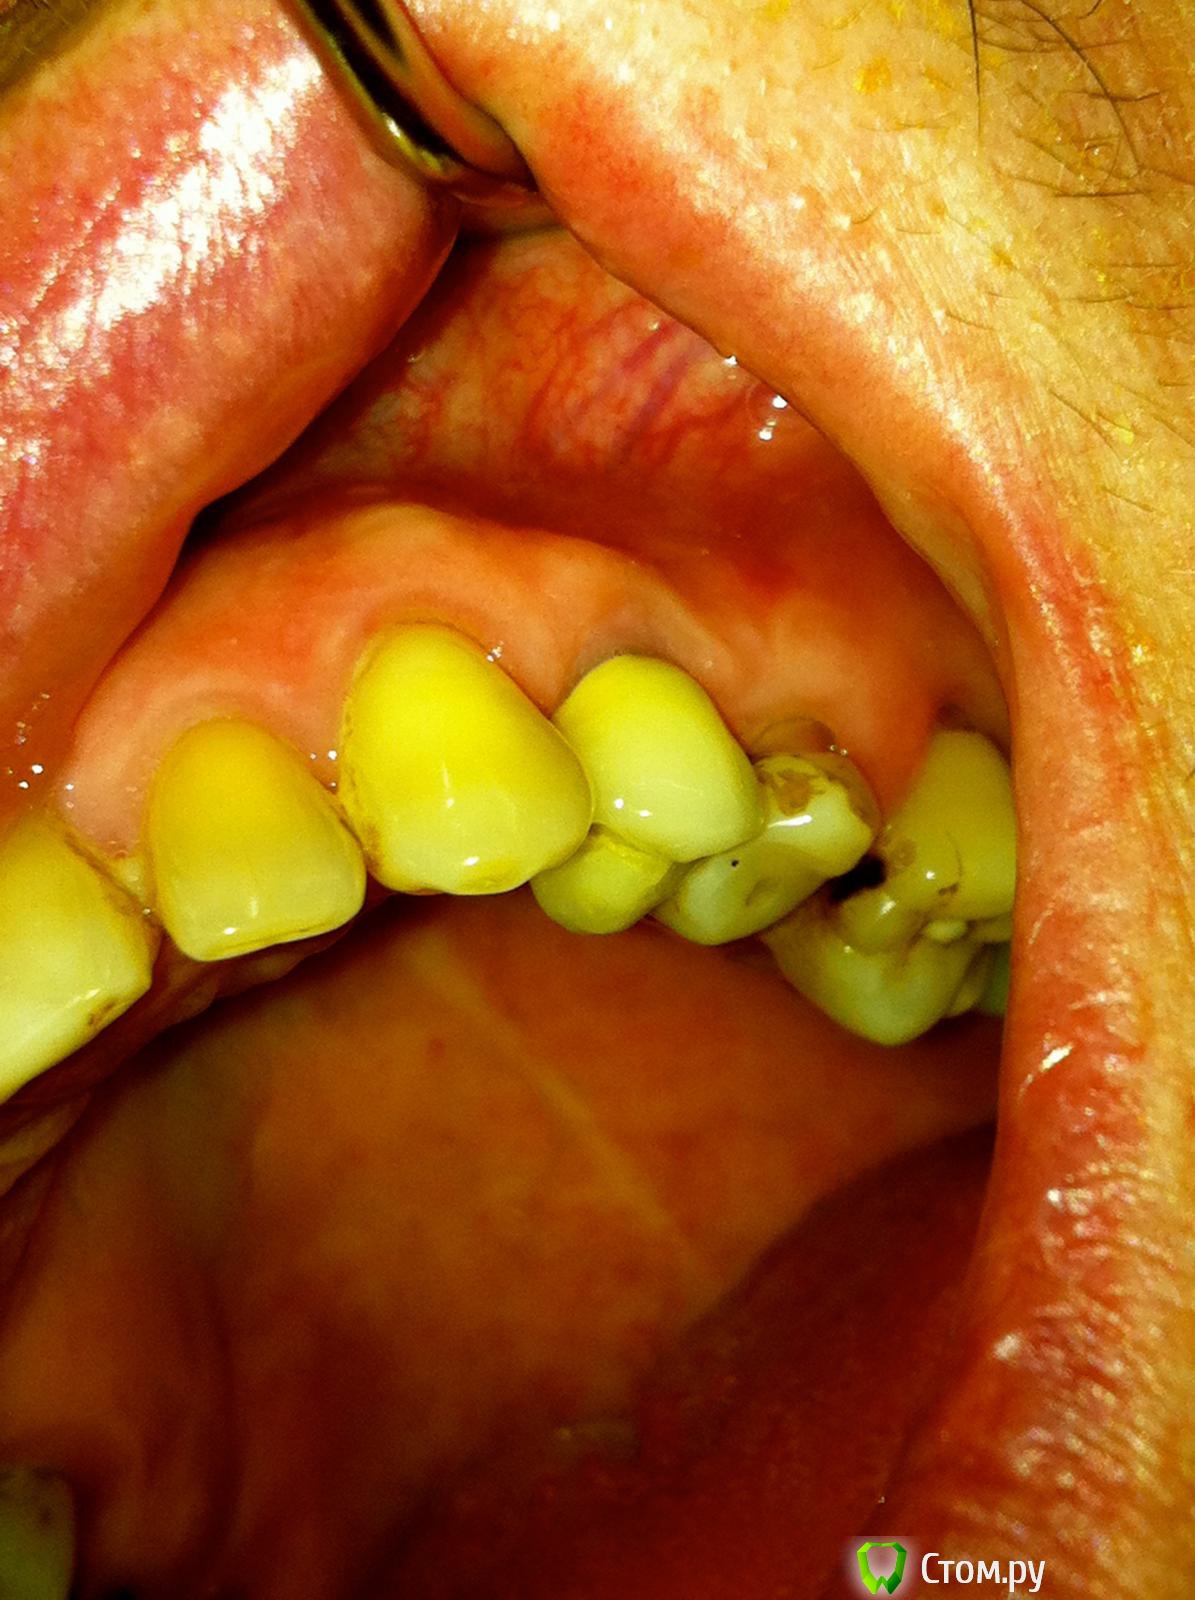

Tabula Rasa Опубликовано 29 сентября, 2014 Поделиться Опубликовано 29 сентября, 2014 (изменено) Пациент Л, 65 летИмплантация в области 2.4. Ожидание 4-4.5 месяца->недостаток мягких тканей и к тому же явный "завал" вестибулярного овала->ротированный лоскут на ножке одновременно фиксируемый формирователем->1 месяц->протезирование.Окончательным результатом не до конца доволен,т.к десна все равно усела и по высоте,и по ширине...думается ошибка в отсутствие временной коронки на импланте была. Изменено 29 сентября, 2014 пользователем IlyaPM Ссылка на комментарий

Евгений Ходыкин Опубликовано 30 сентября, 2014 Поделиться Опубликовано 30 сентября, 2014 С такой гигиеной не опасаетесь за результаты?? Ссылка на комментарий